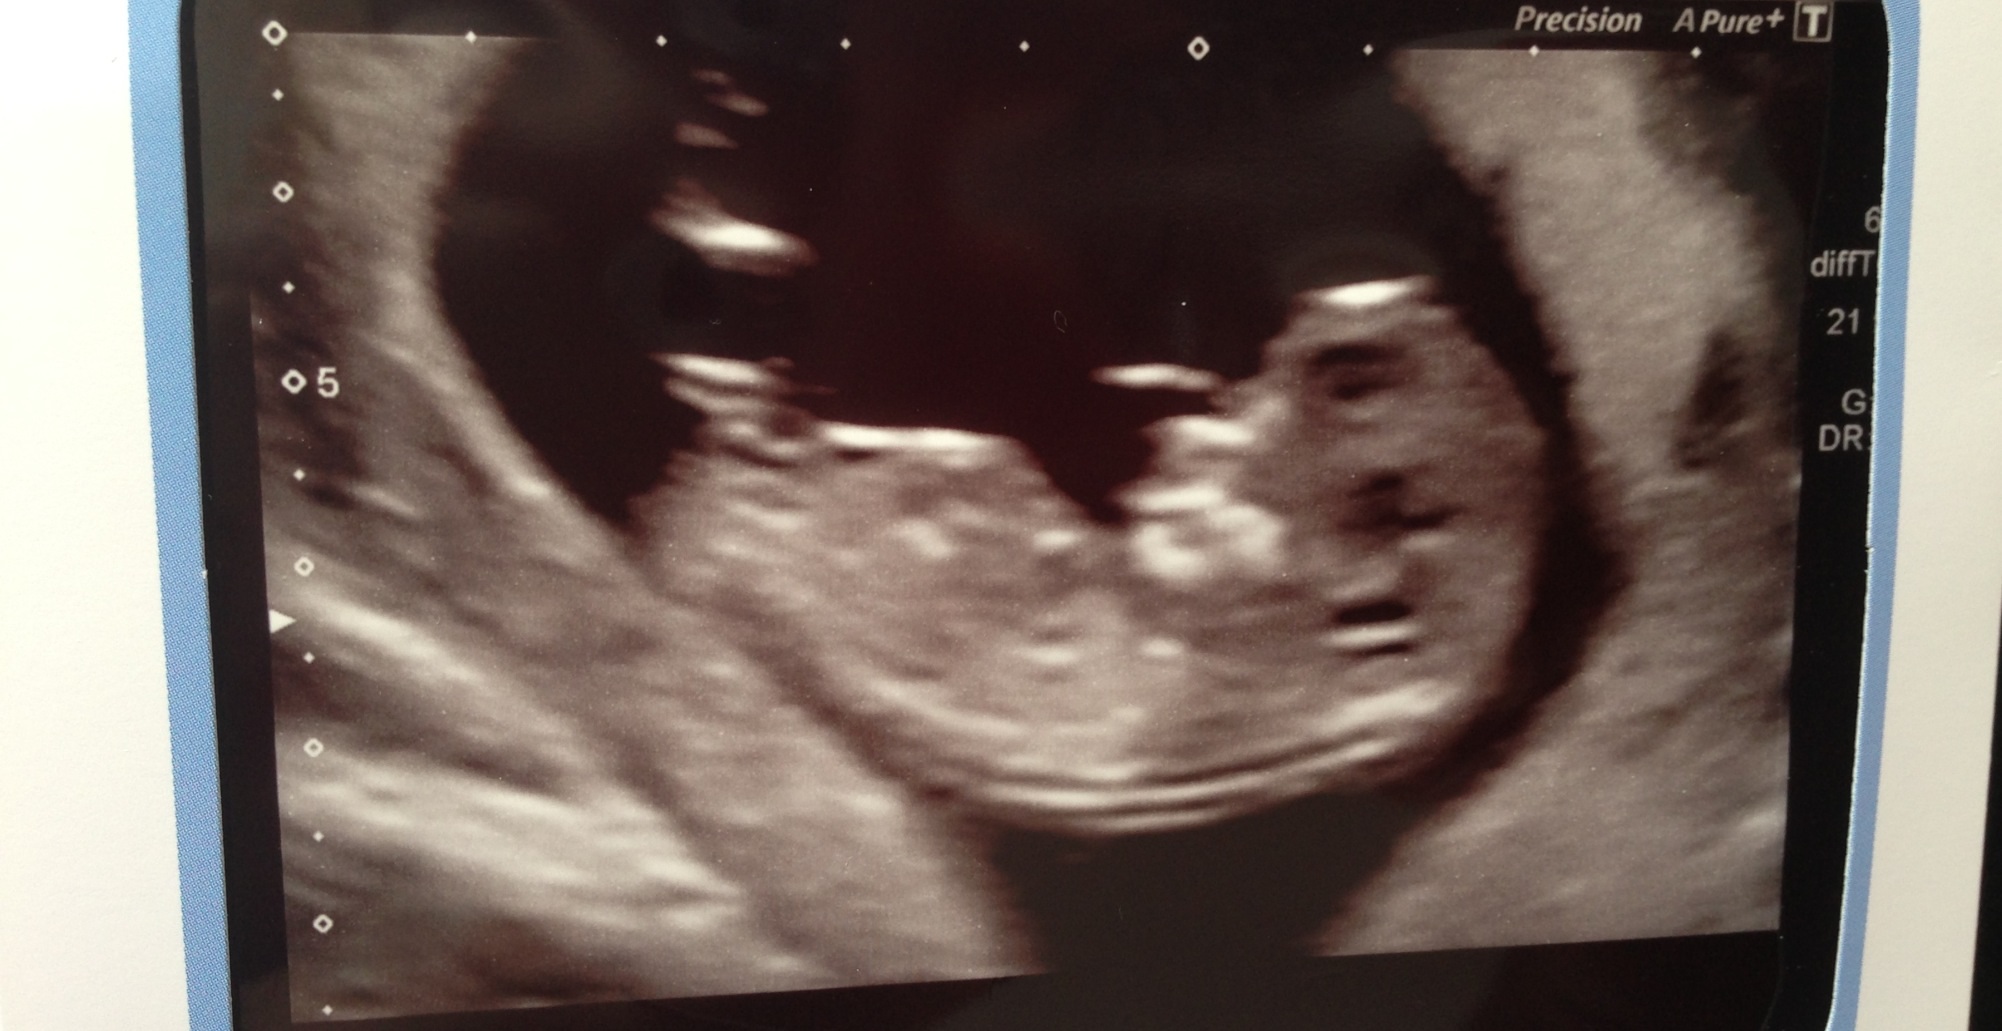

Maybe a girl?

I would say boy..

Not very sure but leaning boy

i think girl as it does look quite flat..

Slight boy lean xx

Looks like it could be on the rise to me so I would say boy xx